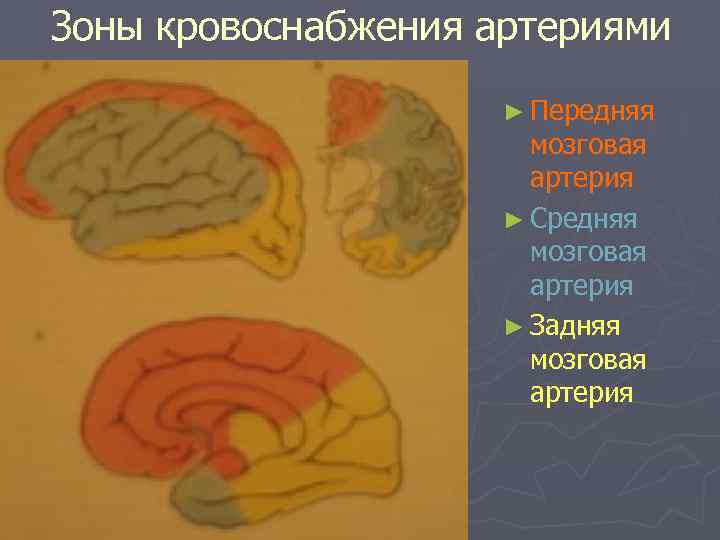

Зоны кровоснабжения артериями ► Передняя мозговая артерия ► Средняя мозговая артерия ► Задняя мозговая артерия